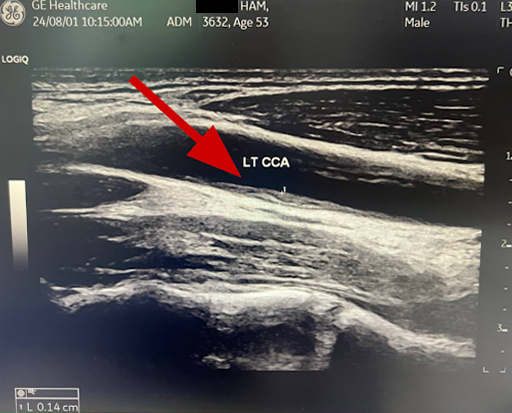

Before: RT CCA . Longitudinal . Baseline

Before: LT CCA . Longitudinal . Baseline

After: Plaque remodeling and reversal. B-mode ultrasound imaging of the carotid artery. Kevin Ham, MD, 2025. Three months on the CAST protocol: WFPB diet, high-intensity cycling, structured fasting, targeted supplementation.